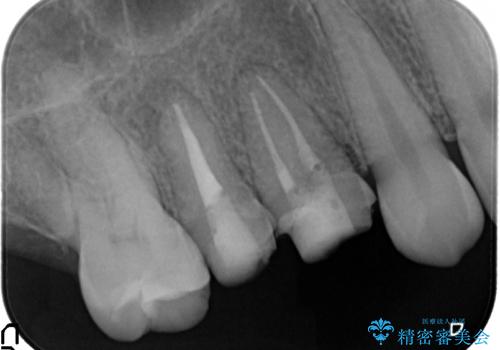

インプラントを用いた臼歯部欠損補綴

- 上下1本づつの歯を失い、噛めないことの改善を求めて来院されました。

保存可能な歯の虫歯・根管治療を行い、喪失した部分はインプラントを埋入、オールセラミックジルコニアクラウンを製作し審美的に仕上げていきます。

今回下顎の欠損部位はブリッジも検討されましたが、並行性の観点から最後方臼歯の神経を取るリスクを抑えるためインプラント治療を選択しました。